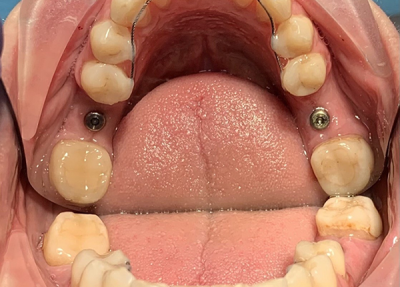

Пациент (30 лет), адентия 46 зуба, 36 периодонтит.

Установлено 2 импланта, 36 с одномоментной имплантацией в лунку удаленного зуба.

Проведена коррекция десневого контура (ССТ с бугра верхней челюсти).